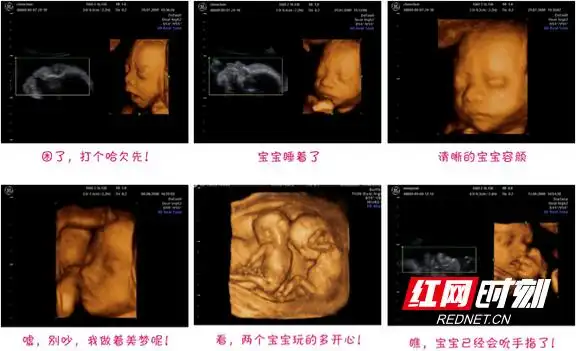

b超检查中宝宝的各种姿态.